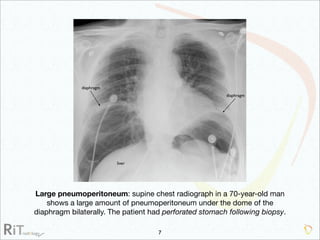

The document discusses the imaging modalities used in evaluating acute abdominal pain, including radiography, ultrasound, computed tomography (CT), and scintigraphy, highlighting their roles, indications, and limitations. It emphasizes the complexity of diagnosing acute abdomen due to its broad differential diagnoses and the necessity for accurate imaging to inform timely management. Additionally, the document outlines considerations such as patient history, contrast medium reactions, and appropriate imaging criteria based on various clinical presentations.